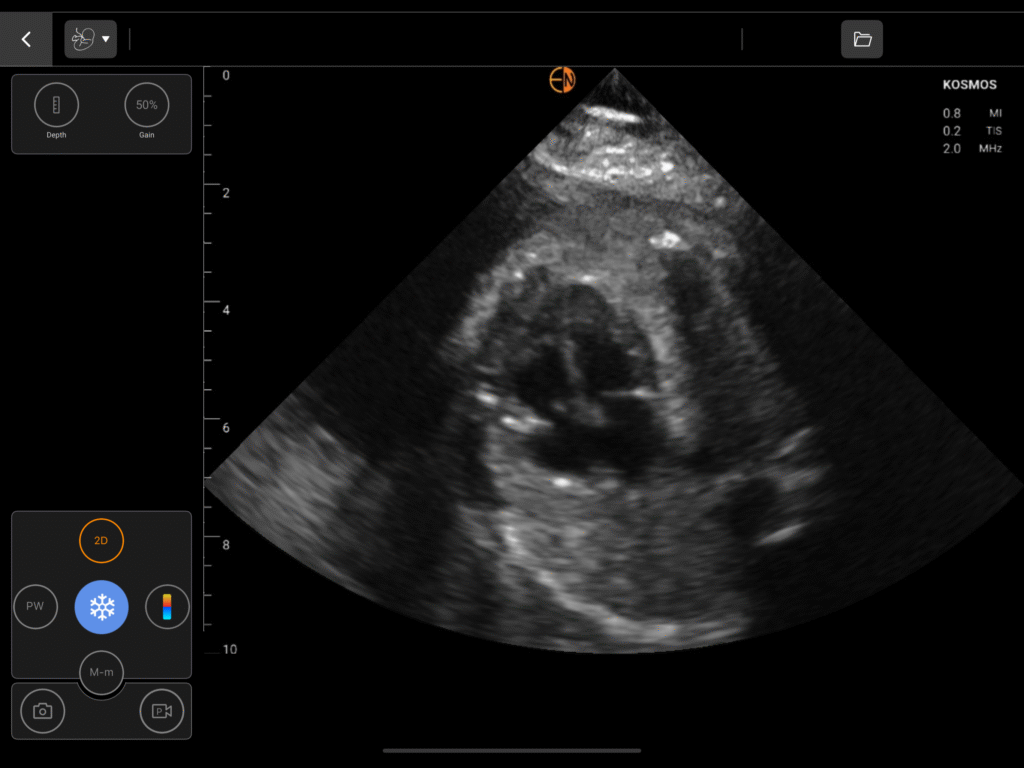

Complete GYN Package

Dedicated measurements for the uterus, endometrium, ovaries, including volume calculations for cysts and masses, and bladder.

OB/GYN Image Gallery